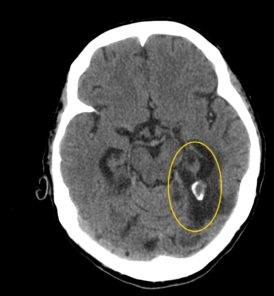

image

Киста на компьютерной томограмме

Рацемозная форма сопровождается образованием множества гроздевидных пузырей внутри церебральной структуры. Полости имеют соединительнотканную капсулу. Вокруг образований находится соединительнотканная оболочка.

Ранние стадии кистообразования показывает МРТ с контрастом или без него. КТ мозга при кисте верифицирует крупные полости с утолщенной стенкой.